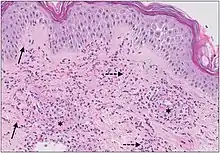

| Example of hypersensitivity vasculitis | |

The small vessels in the skin affected are located in the superficial dermis and include arterioles (small arteries carrying blood to capillaries), capillaries, and venules (small veins receiving blood from capillaries).[5] In general, immune complexes deposit in vessel walls leading to activation of the complement system. C3a and C5a, proteins produced from the complement system, attract neutrophils to the vessels.[9] Once activated, neutrophils then release preformed substances, including enzymes causing damage to vessel tissue.[9] Evidence of this process can be seen with a sample of removed skin tissue, or biopsy, viewed under a microscope. Neutrophils are seen surrounding blood vessels and their debris within vessel walls, causing fibrinoid necrosis. This finding on histological examination is termed "leukocytoclastic vasculitis".[5]